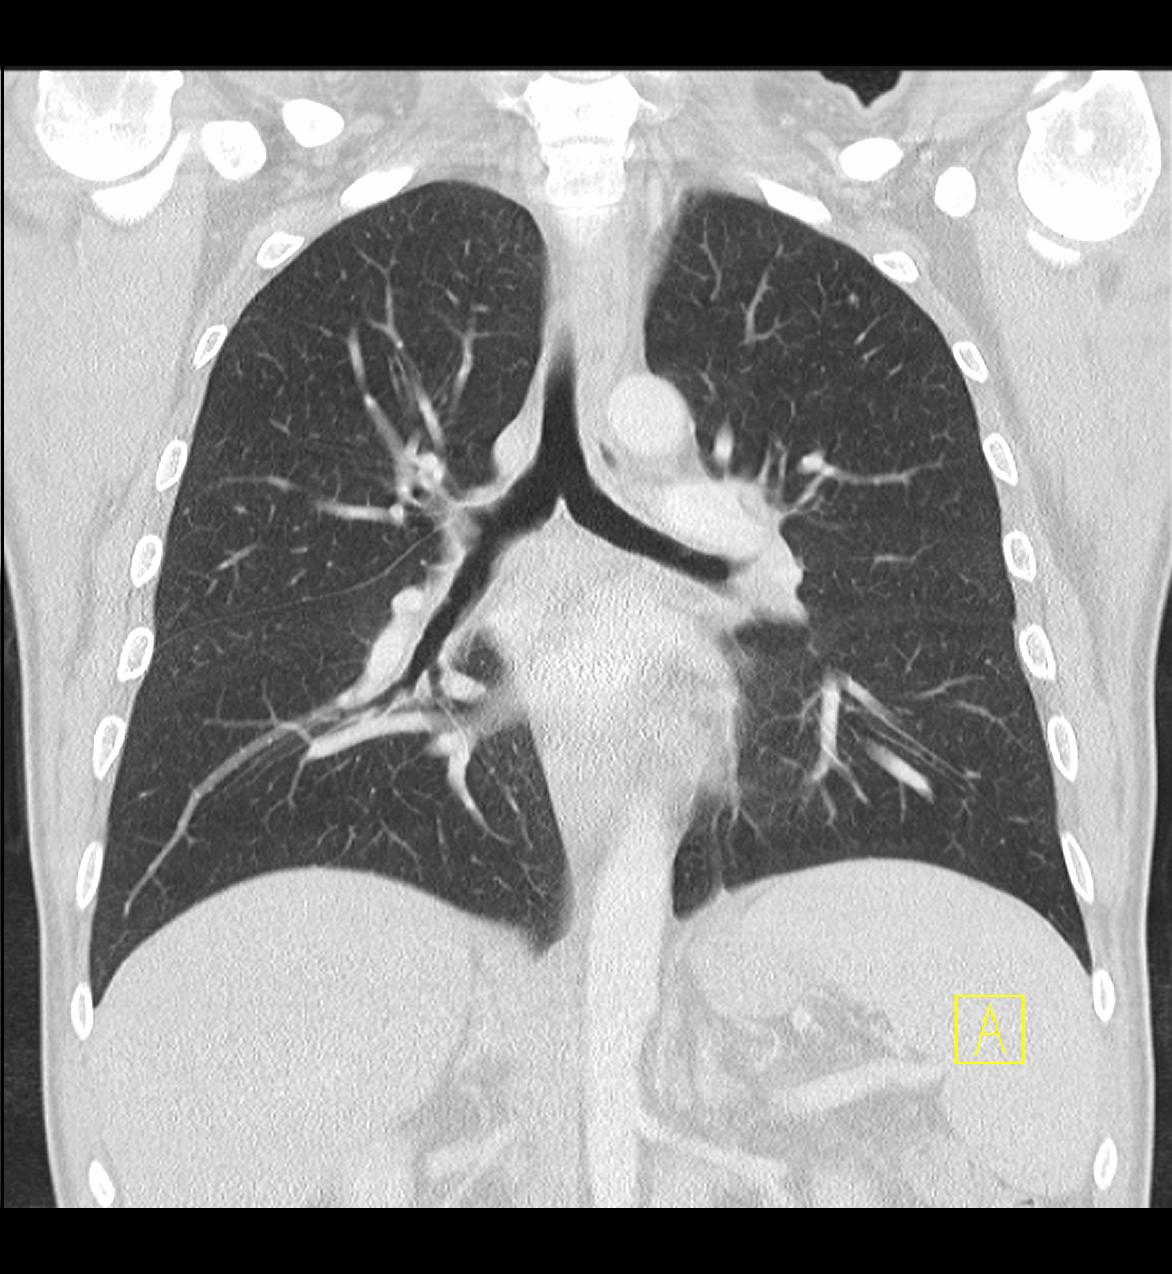

Das Klinikum Ludwigshafen verfügt über einen Kardio-CT der neuesten Generation: Das 128-Zeilen-Gerät ermöglicht eine äußerst präzise Untersuchungsmethode zur Darstellung der Herzkranzgefäße des schlagenden Herzens.

Die koronare Herzerkrankung (KHK) ist eine der häufigsten Erkrankungen in der westlichen Welt. Bei dieser Erkrankung führen Kalkablagerungen an der Gefäßwand (Arteriosklerose) zur Verengung des betroffenen Gefäßes. Diese Engstellen (Stenosen) vermindern die Blutversorgung des Herzmuskels. Kommt es mit dem Fortschreiten der KHK zum Gefäßverschluss, entsteht ein Herzinfarkt.

Die Computertomografie des Herzens (Kardio-CT) ist eine Methode, die frühen Stadien der KHK zu erkennen, bzw. eine KHK mit an Sicherheit grenzender Wahrscheinlichkeit ausschließen zu können.

Prinzipiell ist die Kardio-CT eine Computertomografie (CT), also eine Röntgenuntersuchung, bei der die Röntgenröhre spiralartig um den Patient rotiert. Das Besondere ist die enorme Leistungsfähigkeit der CT, bei der mehrere, sehr dünne Schichten pro Umdrehung gleichzeitig aufgenommen werden.

In Ludwigshafen verwenden wir einen CT der neuesten Generation der Firma Siemens, mit dem wir 128 Schichten pro Umdrehung aufnehmen. Auf diese Weise lässt sich das gesamte Herz mit nur vier bis fünf Umdrehungen erfassen. Für Sie bedeutet das, dass wir Ihre Herzkranzgefäße in der derzeit bestmöglichen Auflösung und mit geringst möglicher Strahlenbelastung darstellen können.